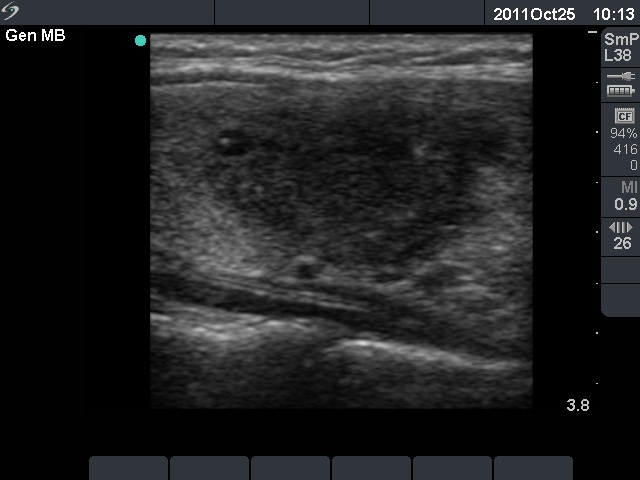

Subacute granulomatous thyroiditis - case 855

Follow-up -

11 months

after initial investigation (ultrasonographic picture 2)

Right lobe, longitudinal scan.